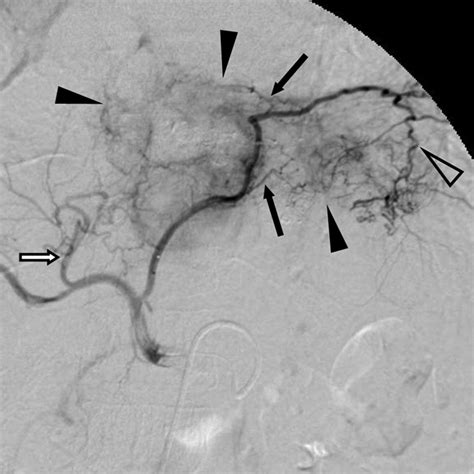

Learn about the anatomy and clinical significance of the inferior phrenic artery. This guide explores its crucial role in vascular supply, its frequent involvement in hepatocellular carcinoma blood supply, and its relevance in interventional radiology procedures, including arterial embolization and complex diagnostic imaging techniques. Understand how this vital vessel impacts surgical planning and patient outcomes in clinical practice.